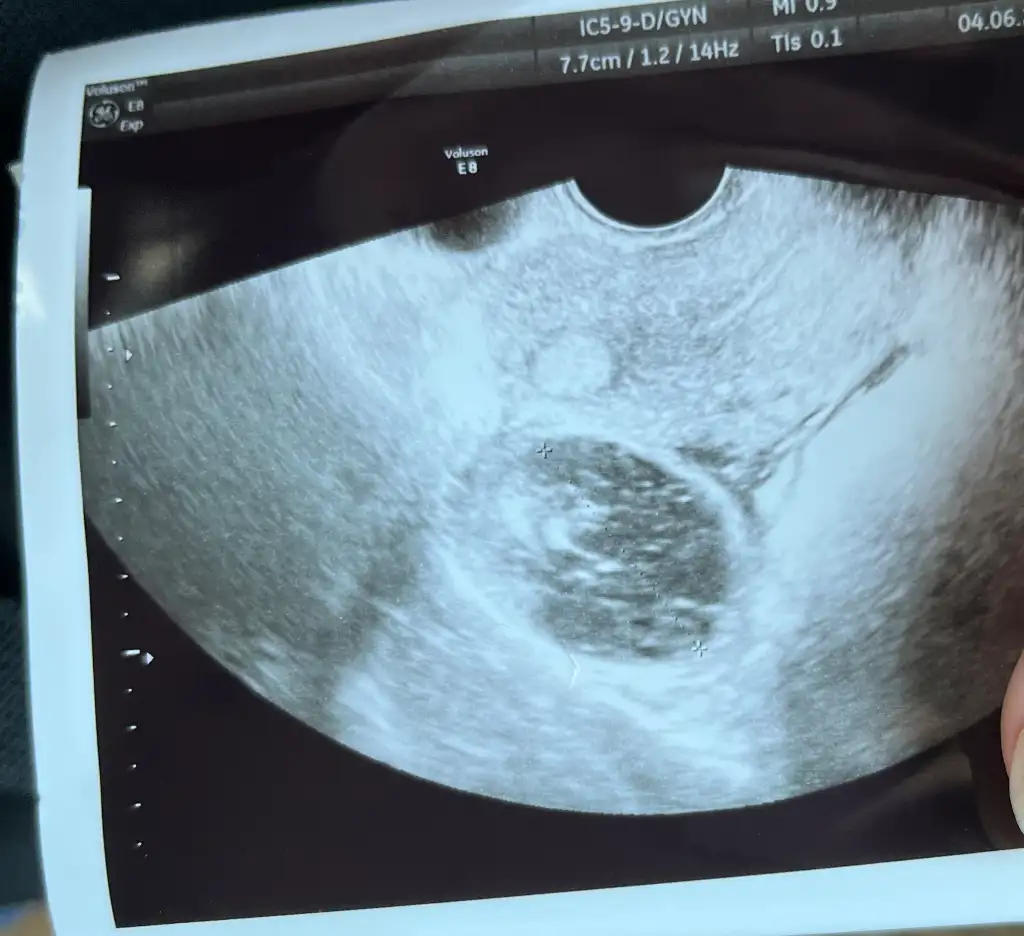

Soğan kürü kistimi patlatmıştı benim aman diiym. İnositol destekliyor da neden kiste dönüşüyor çözemedim benim de 3.37 yazıyor usg de nedir derdi anlamamİnositol mu acaba çok büyütüyor benim de soğan kürü yaptığım ay 3.7 cm kist oldu.

Bana 37 mm denmişti yani 3.7 cm oluyor bi daha atıldı geçti heralde sonraki aylarda yoktu kontrolsüz östrojen de yumurtayı olması hetkeitipinden çok büyütüyor takviyeyi kesin bide öyle baktırınSoğan kürü kistimi patlatmıştı benim aman diiym. İnositol destekliyor da neden kiste dönüşüyor çözemedim benim de 3.37 yazıyor usg de nedir derdi anlamam

Enfeksiyon için soğan kürü deneyeyim dedim yumurtam kist olmuş içi boş kist adetle atılır dediler.

Hormonları bozdugu için catlamiyor olabilir mi canım? Benim bilgim yok ama ben de kullanmayı düşünüyorum. Yumurta takibi yapıp yeterli büyüklüğe gelince doktor çatlatma iğnesi verse yine aynı mi olur?Soğan kürü kistimi patlatmıştı benim aman diiym. İnositol destekliyor da neden kiste dönüşüyor çözemedim benim de 3.37 yazıyor usg de nedir derdi anlamam

Her doktor inositolun yumurtayı olgunlaşıp çatlamasını desteklediğini söylüyor. Ben 2 binlik kullanıyorum böyle kullanılması gerekiyormuş. Aşılama yaptırdım ovitrelle vuruldum onda bile kiste dönüştü yani ne oluyor çözemiyoruz. Şimdi tekrar iğneyi arıyorum bulamıyorumHormonları bozdugu için catlamiyor olabilir mi canım? Benim bilgim yok ama ben de kullanmayı düşünüyorum. Yumurta takibi yapıp yeterli büyüklüğe gelince doktor çatlatma iğnesi verse yine aynı mi olur?